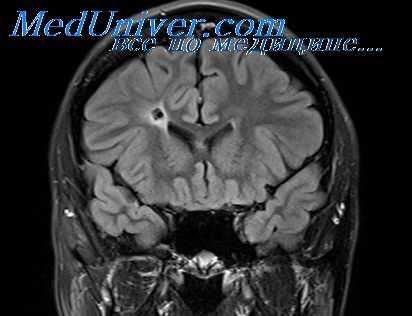

МРТ головного мозга — более точный метод диагностирования. При проведении МРТ на первых стадиях формирования абсцесса мозга (1-9 сутки) энцефалитический очаг выглядит: на Т1-взвешенных изображениях — гипоинтенсивным, на Т2-взвешенных изображениях — гиперинтенсивным. МРТ на поздней (капсулированной) стадии абсцесса головного мозга: на Т1-взвешенных изображениях абсцесс выглядит, как зона пониженного сигнала в центре и на периферии (в зоне отека), а по контуру капсулы сигнал гиперинтенсивный. На Т2-взвешенных изображениях центр абсцесса изо- или гипоинтенсивный, в периферической зоне (зоне отека) гиперинтенсивный. Контур капсулы четко очерчен.